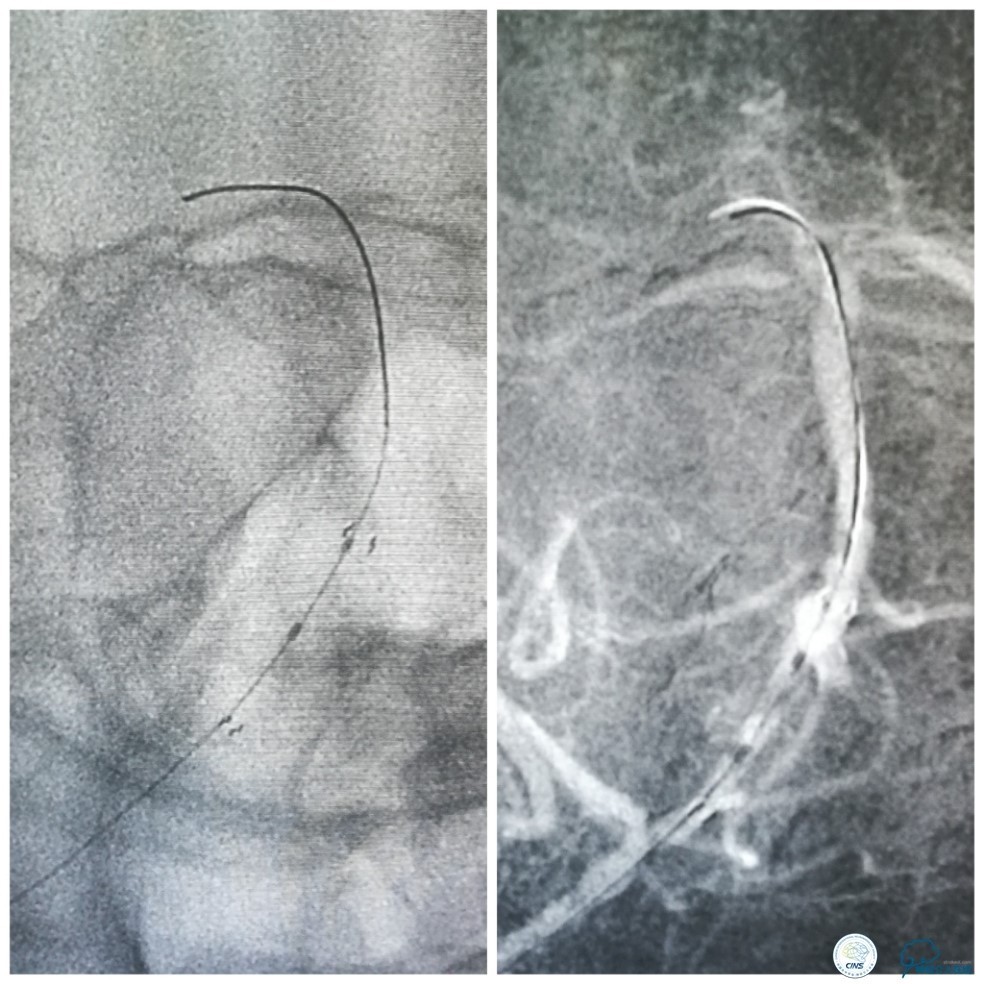

全麻下右侧股动脉穿刺置入8F动脉鞘,6F导引导管到位,送入Traxcess(0.014″200cm)微导丝+Echelon-10微导管小心通过右侧椎动脉V1段狭窄处至V2段远端,交换撤出Traxcess微导丝,送入Transend(0.014″300cm)微导丝至V2段远端(图10)。

图10

Ultra-Soft球囊(3.0mm×20mm)于狭窄处预扩张后置入EXCEL支架(4.0 mm× 24mm),球扩后造影见支架贴壁良好,远端血管显影好,前向血流TICI3级。6F导引导管沿微导丝通过右椎动脉V1段支架至V2段(图11)。

图11

此时多体外投照显示右椎V4-基底动脉极重度狭窄,几近闭塞(图12)。

图12